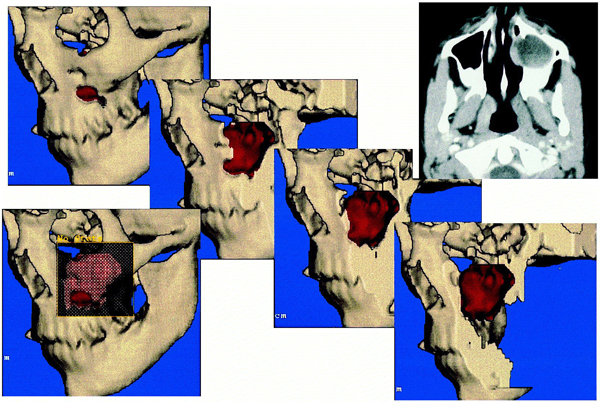

I numeri sono pochi, anche se in aumento: 300 casi all’anno, 1 ogni 100 mila abitanti. Ma le tecniche chirurgiche di intervento per i tumori del naso e paranasali – un tumore nel 42% dei casi professionale, dovuto all’esposizione ad agenti tossici (polveri, solventi organici, metalli) e con prevalenza maschile (2,9%) – fanno scuola e aprono nuovi orizzonti: sfruttare le vie anatomiche naturali per raggiungere il bersaglio chirurgico, con una migliore qualita’ dell’immagine in alta definizione (HD) e l’acquisizione della terza dimensione (profondita’ in 3-D), e’ infatti divenuto il moderno approccio della chirurgia endoscopica.3d_naso La tecnica e’ oggi applicata nell’80% dei casi al trattamento delle malattie infiammatorie nasosinusali e benigne del basi-cranio e, in casi selezionati, anche per la malattia maligna. A certificarlo sono gli ottimi benefici: eradicazione quasi completa del tumore (nelle situazioni piu’ favorevoli e con minore compromissione fino all’80% di malattia), possibilita’ di interventi in day hospital per la patologia infiammatoria, con anestesia locale, rapido recupero e traumatismi quasi invisibili. Non meno importanti sono i vantaggi per la patologia maligna: miglioramento a un anno in termini di qualita’ della vita e di sopravvivenza media (di norma a 5 anni e’ del 47% negli uomini e 51% nelle donne), riduzione di complicanze perioperatorie. Le novita’ tecnologiche e chirurgiche, sono sviluppate tutte in direzione della mininvasivita’, dell’imaging per la migliore definizione dell’estensione dei tumori per l’identificazione dei sottotipi di malattia.In validazione anche l’utilizzo del robot, tecnica promettente ma ancora ‘ingombrante’ per i seni paranasali e la base cranio.